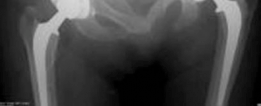

This image depicts a typical hybrid THA construct, showcasing a cemented femoral stem and an uncemented acetabular cup. The distinct fixation mechanisms are visually apparent.

* Anteroposterior (AP) Pelvis with both hips: Essential for assessing hip center of rotation, leg length discrepancy, femoral head migration, osteophyte formation, and overall pelvic obliquity. This view allows comparison of both hips and identifies any pelvic tilt.